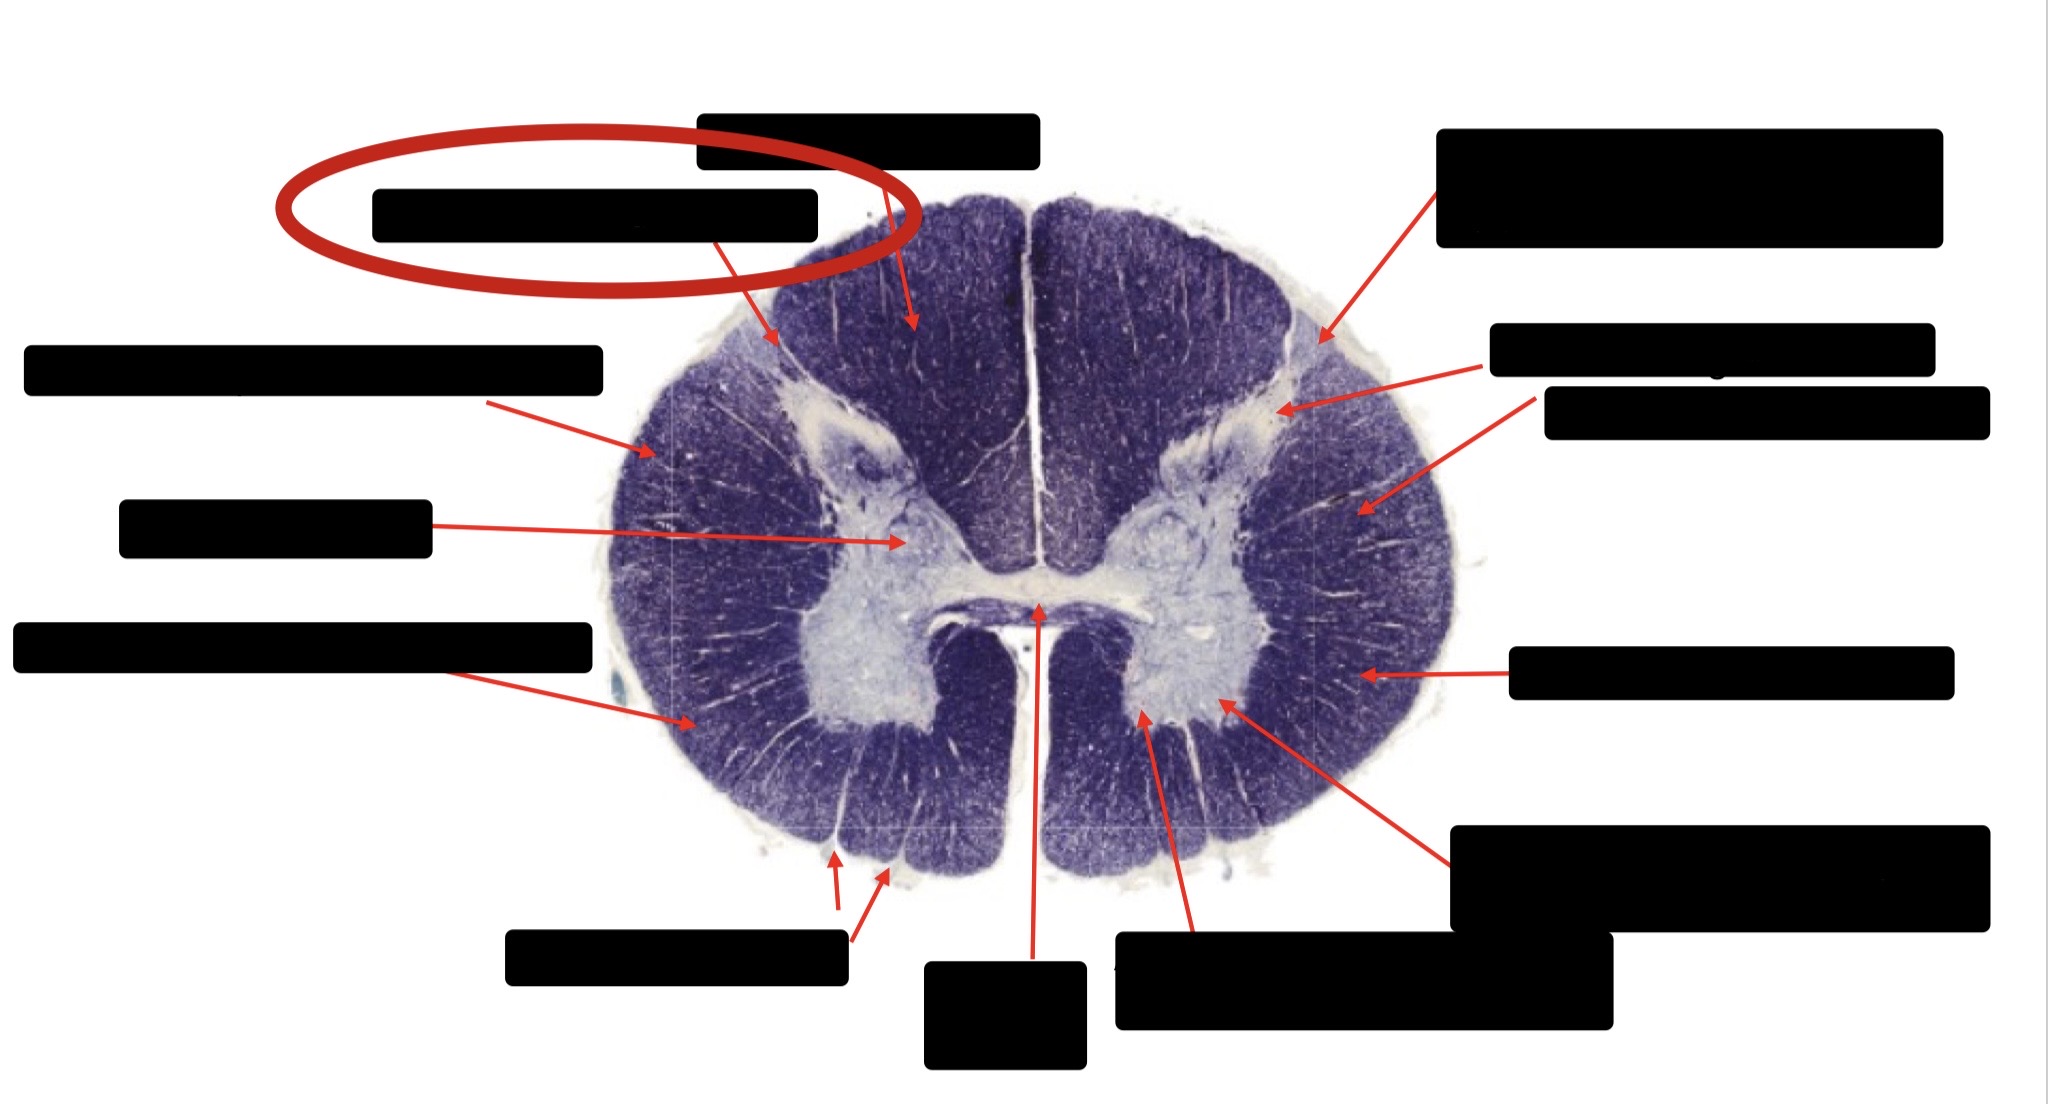

Anterior Spinal Artery

Denticulate Ligament

Ventral Root

Dorsal Root

Posterior Column Fasciculus Gracilis

Large Fiber Entry Zone

Central Canal

Dorsal Rootlet

Lissaeur’s Tract & Small Fiber Entry Zone

Substantia Gelatinosa

Lateral Corticospinal Tract

Anterior Horn Motor Neuron

Spinothalmic Tract

Anterior Horn Motor Neurons